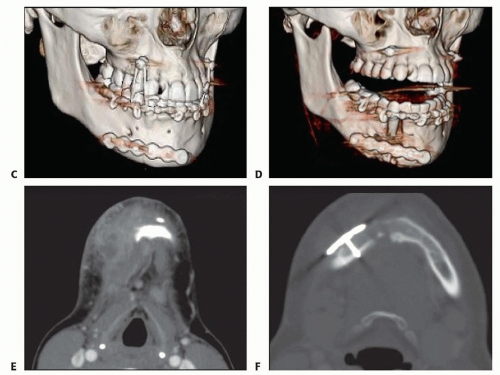

Plain x-ray films (facial series, panoramic) can be used for postoperative evaluation to identify an enlarging gap in the fracture line, presence of irregular radiolucency, and/or hardware loosening (FIG 1A, B).

Maxillofacial computed tomography (CT) with threedimensional formatting has become the imaging modality of choice for evaluation of the fracture site, extent of soft tissue infection, and associated osteomyelitis (FIG 1C-F).